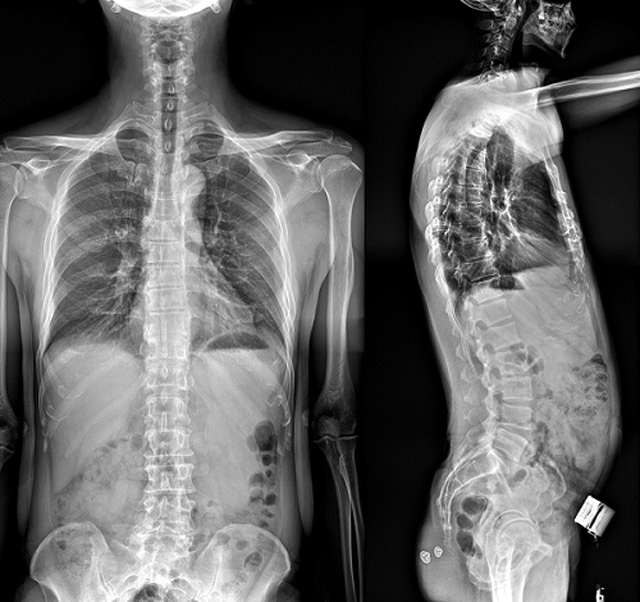

(7)全身拼接功能對有較大尺寸全脊柱拼接圖接桂成金下股分成幾次拍攝,再經(jīng)過秋件開在骨科開展的全脊柱畸形矯治工作中,雖然CT. MRI也能獲取全脊柱影像,接圖像,以便于長度、角度、力線等測量和察脊柱在重力情況下但不能進(jìn)行立位檢查,無法觀全景觀察。全身拼接功能是高等級DR攝取患者立位全下的功能狀態(tài)圖像,因此采用動態(tài)醫(yī)院特別看重的動態(tài)DR功能之一。注:圖中Cobb脊柱正側(cè)位圖像是首選的檢查方法角度的大小是反映側(cè)彎嚴(yán)重程度的一個標(biāo)準(zhǔn)。